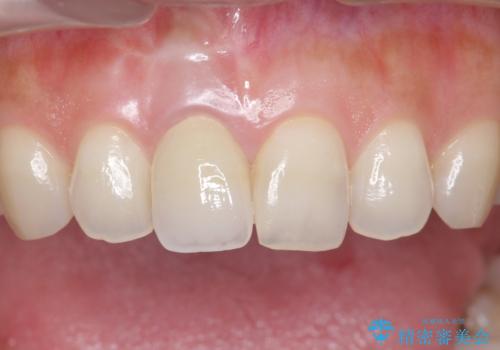

- もっと自然にみえるような差し歯にしたいと希望され来院された患者様です。

患者様の天然歯はグラデーションがあり切縁(歯冠の先端)はやや透けていて透明感があるのに対し、前歯(右上1)の差し歯はやや黄色く不透明で単調な色味でした。

患者様のご希望により、右上1はジルコニアクラウン(スペシャル)、右上5はジルコニアクラウン(スタンダード)へやりかえることにしました。

前歯のクラウンは一度修正し、患者様の理想とする色味や形態を追求しました。

天然歯と見紛うほどの自然な仕上がりに喜んで頂けました。

ジルコニアクラウンの繊細なグラデーション・透明感は熟練した技工士さんの技術の賜物です。

右上1:ジルコニアクラウン スペシャル

右上5:ジルコニアクラウン スタンダード